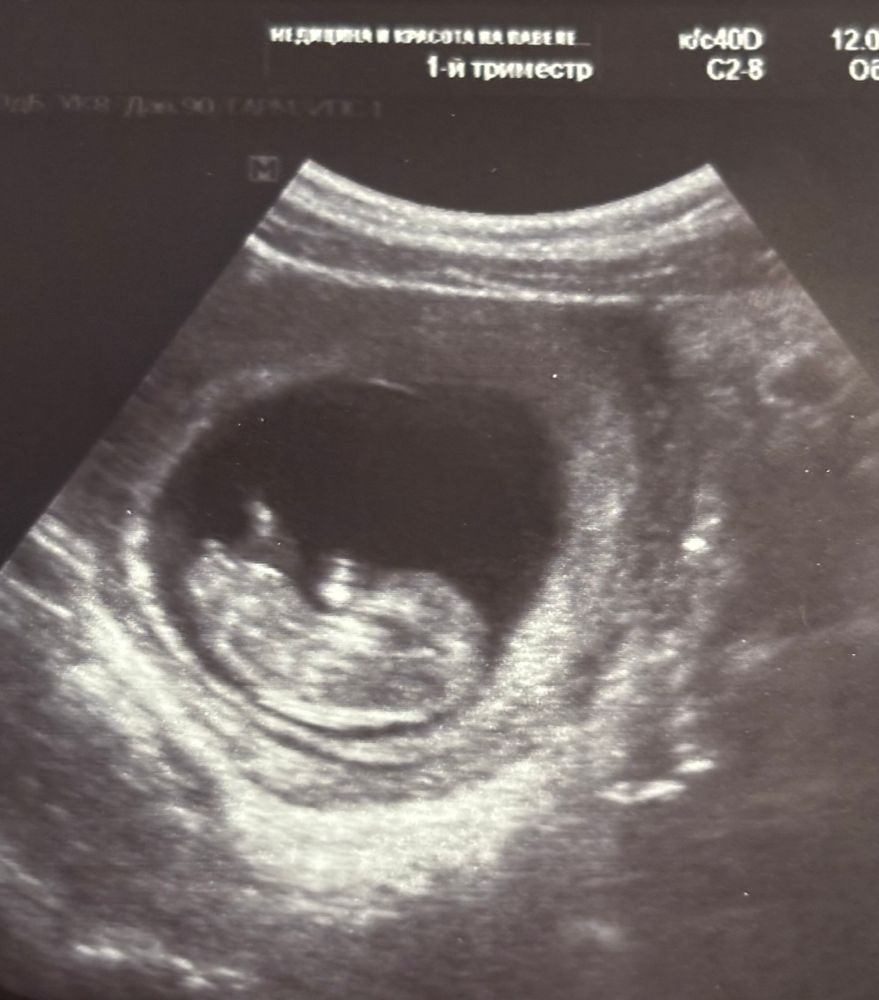

Вот и мы сейчас беременность ведем вроде бы в неплохой клинике. Срок был 10-11 недель, предположили мальчика😡😡я тоже по бугорку вижу, что больше на девочку похоже. Не знаю, может, врачи не по нему определяют. Да и не понимаю, зачем так рано говорить, если неточно( но вроде бы девочки чаще просто другой стороной располагаются, и по форме головки. Ой, сложно это все, короче 😅